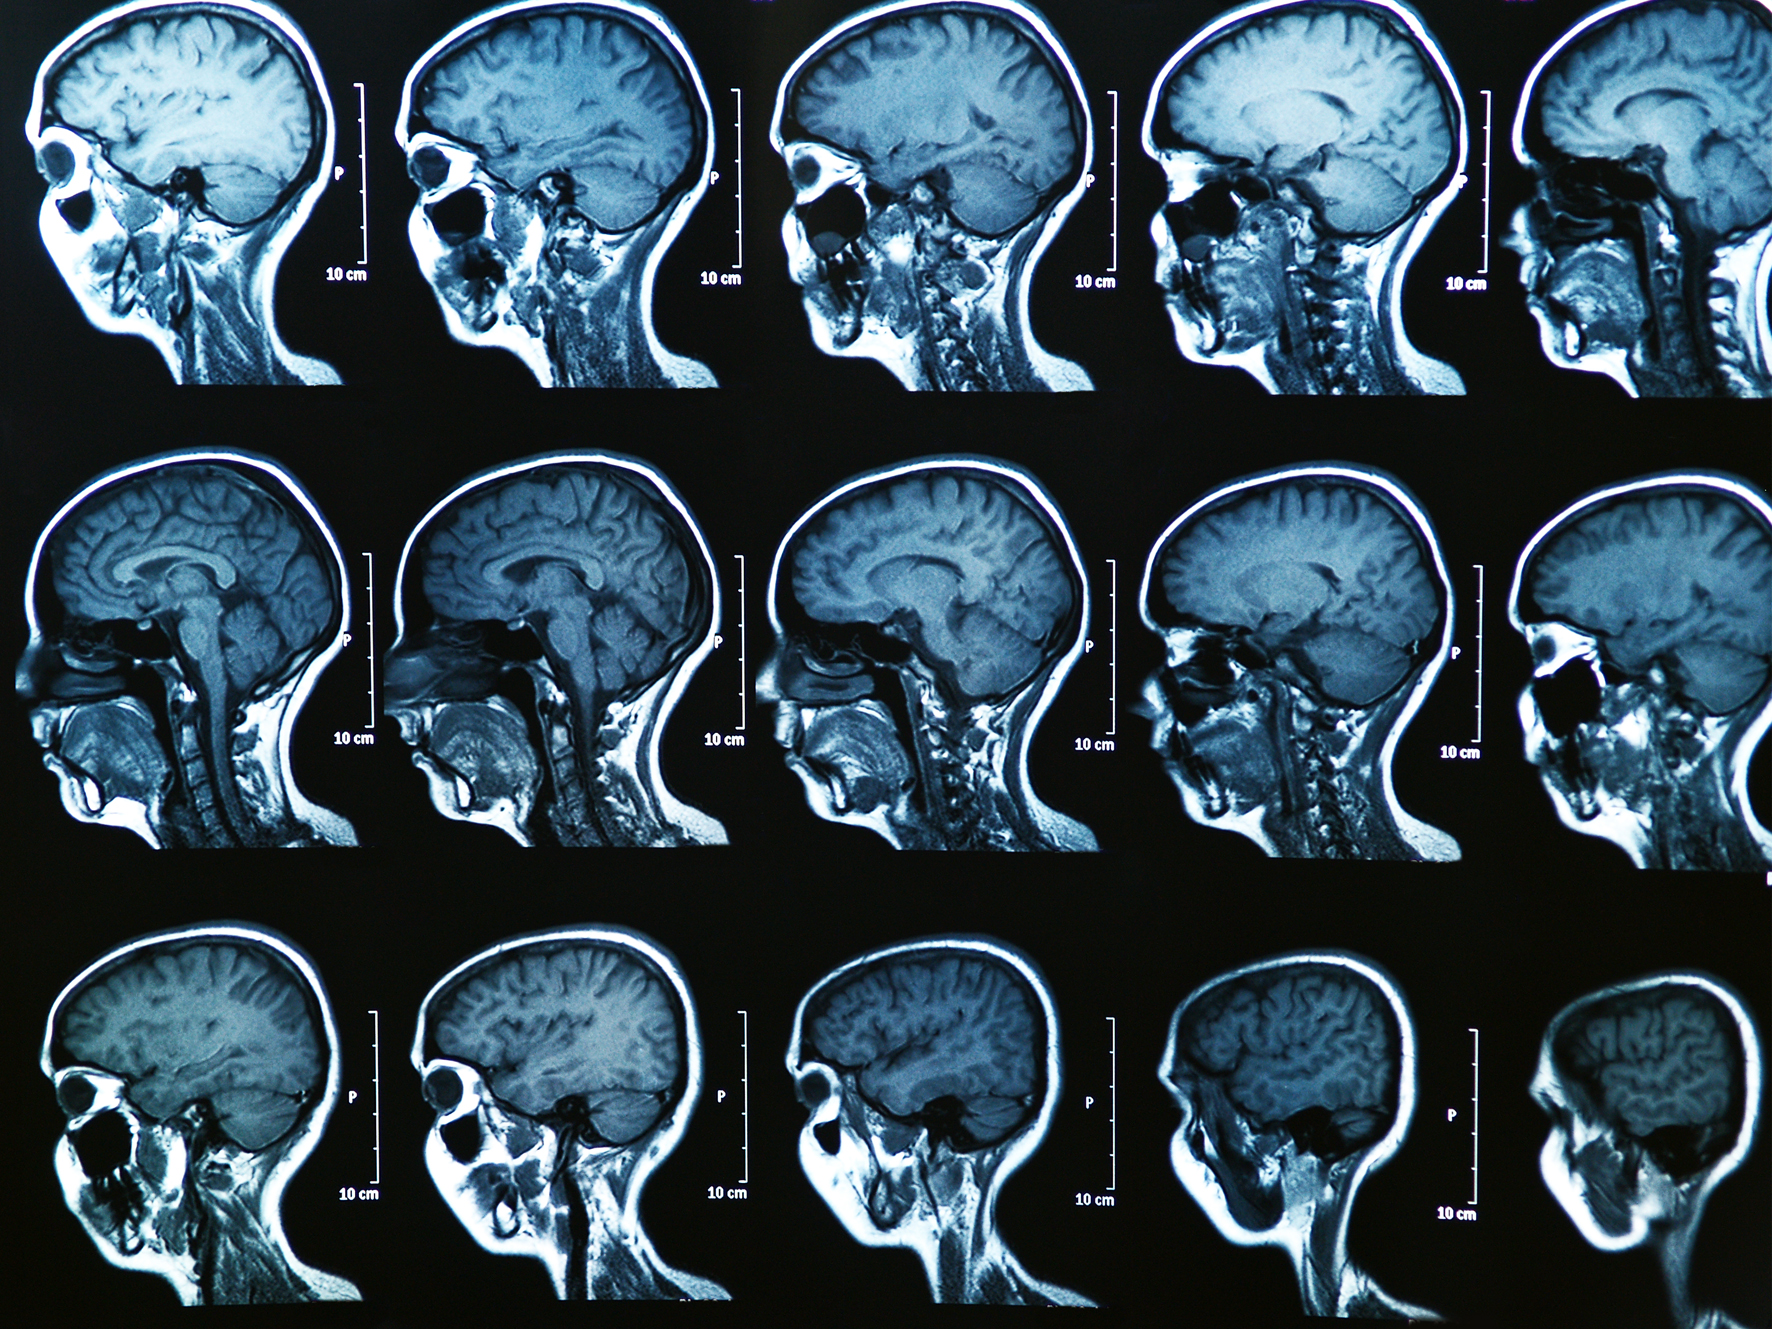

Die medizinische Bildgebung ist ein wichtiges Werkzeug für Diagnostik und Therapie (hier: MRT-Aufnahme eines menschlichen Gehirns)<address>© Symbolfoto: colourbox.de/Bunyos</address>

Die medizinische Bildgebung ist ein wichtiges Werkzeug für Diagnostik und Therapie (hier: MRT-Aufnahme eines menschlichen Gehirns)

Die medizinische Bildgebung erlaubt es, von außen einen Blick in den Körper zu werfen und verborgene Vorgänge sichtbar zu machen. Sie ist daher für Diagnose und Therapie verschiedener Erkrankungen von Bedeutung. Zunehmend wichtig wird die sogenannte vierdimensionale Bildgebung. Dabei werden dreidimensionale Bilder erzeugt und zusätzlich – als "vierte Dimension" – Veränderungen im Zeitverlauf rekonstruiert und sichtbar gemacht. Dies erlaubt zum Beispiel, Bewegungen durch den Herzschlag oder durch die Atmung zu erfassen und dadurch schärfere Bilder zu produzieren. Die Mathematik spielt dabei eine zentrale Rolle. Ein neues bundesweites Verbundprojekt hat nun das Ziel, die Methoden der "4-D-Bildgebung" zu verbessern. So soll es möglich werden, gleichzeitig Bewegungen zu analysieren und molekulare Prozesse quantitativ zu messen. Quantitativ bedeutet beispielsweise, dass messbar wird, wie viel Zucker die Zellen eines Organs oder Gewebes in einer bestimmten Zeit verbrauchen (Glukosemetabolismus). Das Projekt wird von Prof. Dr. Martin Burger, Mathematiker an der Westfälischen Wilhelms-Universität Münster (WWU), koordiniert.

Die vierdimensionale Bildgebung erfolgt etwa mittels Magnetresonanz-Tomografie (MRT) oder Positronen-Emissionstomografie (PET). Dabei werden Signale aus dem Inneren des Körpers gemessen. Diese Signale liegen aber zunächst nicht in Form von Bildern vor. Nur durch mathematischen Methoden können aus den Messdaten die dreidimensionalen Bilder im Zeitverlauf rekonstruiert werden. "Es ist eine besonders spannende Herausforderung, die Bewegungen von Organen oder von Patienten während einer dynamischen Messung nicht nur zu erfassen, sondern auch zur Verbesserung der Bildqualität zu verwenden", unterstreicht Martin Burger. "Dies erlaubt es dann genauer zu sehen, wie sich Kontrastmittel im Körper verbreiten." Die neuen Methoden seien zum Beispiel bei Untersuchungen des Herz-Kreislaufsystems oder der Nierenfunktion wichtig. Sie sollen dabei helfen, die Funktionsfähigkeit klarer beurteilen zu können und Krankheiten präziser zu diagnostizieren. Das Projekt wird vom Bundesministerium für Bildung und Forschung für drei Jahre mit rund 836.000 Euro aus dem Programm "Mathematik für Innovationen in Industrie und Dienstleistungen" gefördert.